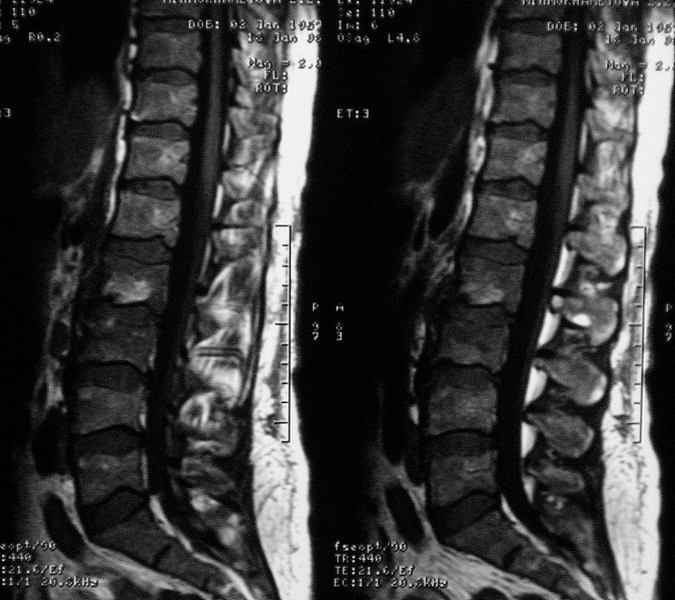

Отправляю MRI в динамике, снятые с пленки на фотоаппарат.

|

MRI через три недели

Данные МРТ выкладываешь некорректно - это не "контроль в динамике", а поход по Сусанинским местам, сравниваемые срезы за разные даты должны быть одинаковыми.